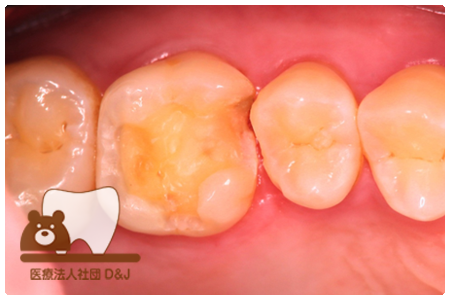

症例4フルジルコニアクラウン 左下6

治療前

治療後

37歳 男性

- 治療内容

- 以前のクラウンがセメントの劣化により外れた為その上にフルジルコニア製の被せ物を装着しました。見た目と強度を両立した自由診療の治療です。

- 治療期間

- 1カ月

- 費用

- 自費

フルジルコニアクラウン:77,000円(税込)

(R8.1月時点)

- その他の治療の費用は含まれておりません。

- リスク・副作用

- 硬い素材のため、かみ合う歯に負担がかかることがあります。将来取り外す場合に歯に負担がかかることがあります。強い力が加わると、まれに欠けたり割れたりすることがあります。